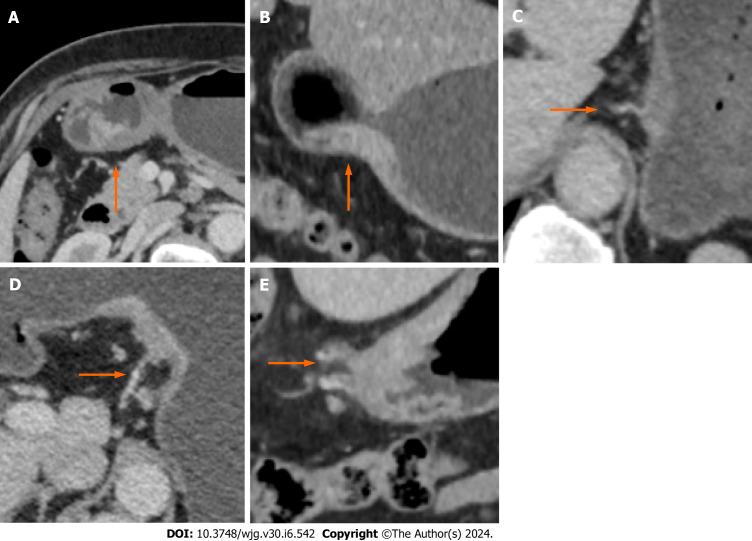

This study used a retrospective dataset involving 257 GC patients (training cohort, = 172; validation cohort, = 85). First, several clinical indicators, including serum tumor markers, CT-TN stages and CT-detected extramural vein invasion (CT-EMVI), were extracted, as were quantitative spectral CT parameters from the delineated tumor regions. Next, a two-step feature selection approach using correlation-based methods and information gain ranking inside a 10-fold cross-validation loop was utilized to select informative clinical and spectral CT parameters. A logistic regression (LR)-based nomogram model was subsequently constructed to predict LVI/PNI status, and its performance was evaluated using the area under the receiver operating characteristic curve (AUC).

RESULTS

In both the training and validation cohorts, CT T3-4 stage, CT-N positive status, and CT-EMVI positive status are more prevalent in the LVI/PNI-positive group and these differences are statistically significant ( < 0.05). LR analysis of the training group showed preoperative CT-T stage, CT-EMVI, single-energy CT values of 70 keV of venous phase (VP-70 keV), and the ratio of standardized iodine concentration of equilibrium phase (EP-NIC) were independent influencing factors. The AUCs of VP-70 keV and EP-NIC were 0.888 and 0.824, respectively, which were slightly greater than those of CT-T and CT-EMVI (AUC = 0.793, 0.762). The nomogram combining CT-T stage, CT-EMVI, VP-70 keV and EP-NIC yielded AUCs of 0.918 (0.866-0.954) and 0.874 (0.784-0.936) in the training and validation cohorts, which are significantly higher than using each of single independent factors ( < 0.05).